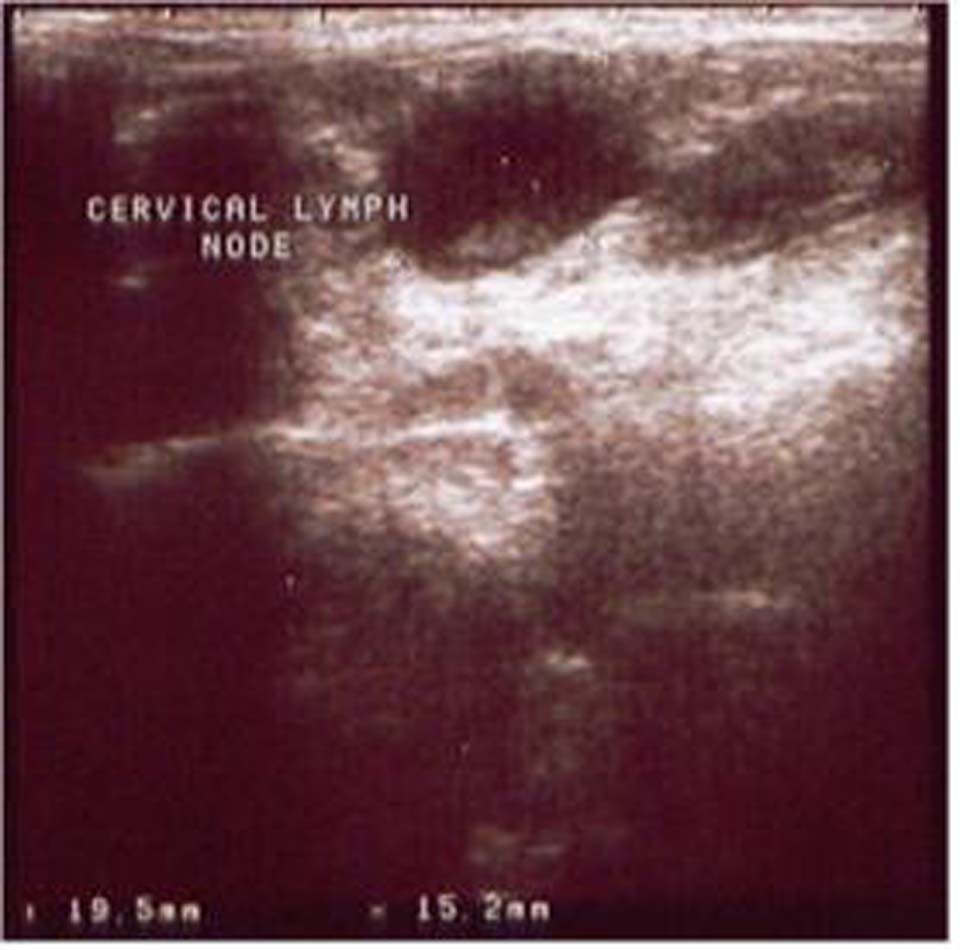

Fig-2. Shows a maximal short axis diameter of 15 mm, a L/S ratio of 1.28 and was proved to be a metastatic enlarged cervical node. Margin in this node was regular with hypoechoic homogeneous echo pattern with absence of hilar echogenicity.